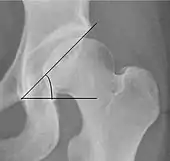

Tönnis angle Slope of the sourcil (the sclerotic weight-bearing portion of the acetabulum) 0 to 10°

• >10° is a risk factor for instability

• <0° is a risk factor for pincer impingement